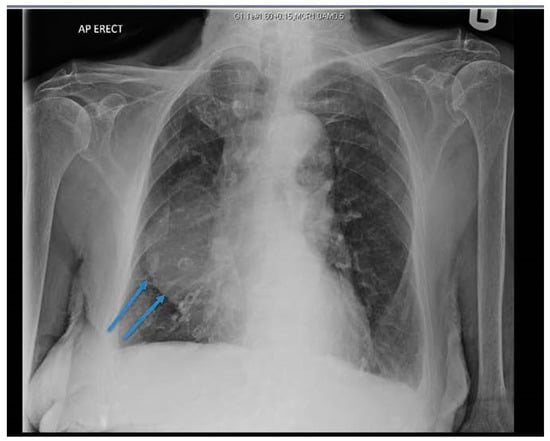

The chest X-ray (CXR) revealed a well-defined hemispherical soft tissue density, projected over the right parahilar region, as shown in Figure 1. No previous CXR was available for comparison. Computerised tomography (CT) of chest, abdomen, and pelvis with contrast demonstrated an 8 cm × 5 cm low attenuation lesion abutting the pericardium, the anterior mediastinum, and anterior chest wall, as shown in Figure 2. The findings were consistent with a large pericardial cyst and no bronchogenic malignancy was identified. Bronchiectatic changes in the middle lobe were consistent with longstanding compression. The patient was treated with intravenous co-amoxiclav and made an uneventful recovery.

Figure 1. Chest X-ray (CXR) showing right sided soft tissue density, hemispherical in shape, projected over the right middle and lower zones (arrows).